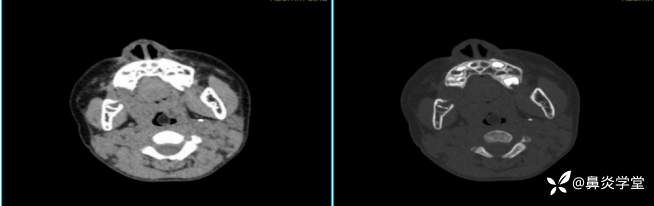

2、鼻咽部增强CT示:鼻咽顶壁软组织增厚,密度均匀,鼻咽左侧壁见片状低密度影,局部呈结节样向腔内突出,最大横截面积约为1.0×1.9cm,平均CT值为 -75HU。

图2:患儿增强CT检查